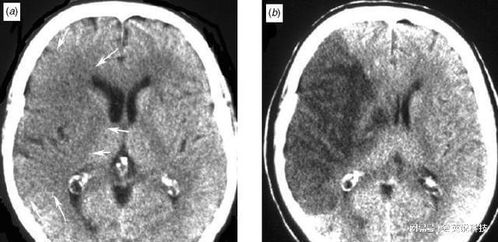

在一个风和日丽的午后,医院里进行了一次特殊的对比研究,研究的主角并非其他,而是两张截然不同的CT片,一张属于一个充满活力的年轻人,年仅25岁;另一张则是一位年近古稀的老人,已经度过了72个春秋,按照常理,这两者的身体状况应该有着天壤之别,令人惊讶的是,他们的CT片上的某些影像竟然如此相似。

我们先来探讨那位年轻的25岁患者,他正处于生命的黄金时期,身体各项功能应该处于巅峰状态,由于现代生活的压力与不良习惯,他的身体已经出现了一些隐患,虽然整体状况良好,但某些器官已经开始出现轻微的退化和炎症。

再来看那位72岁的老人,一般人认为,这个年龄的人身体应该出现了诸多衰老迹象,通过CT片,我们发现老人的身体某些部位虽然有些磨损,但整体结构却相当健康,他的骨骼密度、内脏功能以及血管状况都令人惊讶地保持得很好。

这两张CT片的相似性不仅仅体现在表面上的影像特征,更深层次地揭示了人类身体的复杂性和多样性,为什么一个年轻人的身体会出现老年化的迹象?而一个老年人的身体又能保持如此良好的状态?这背后究竟隐藏着怎样的原因?